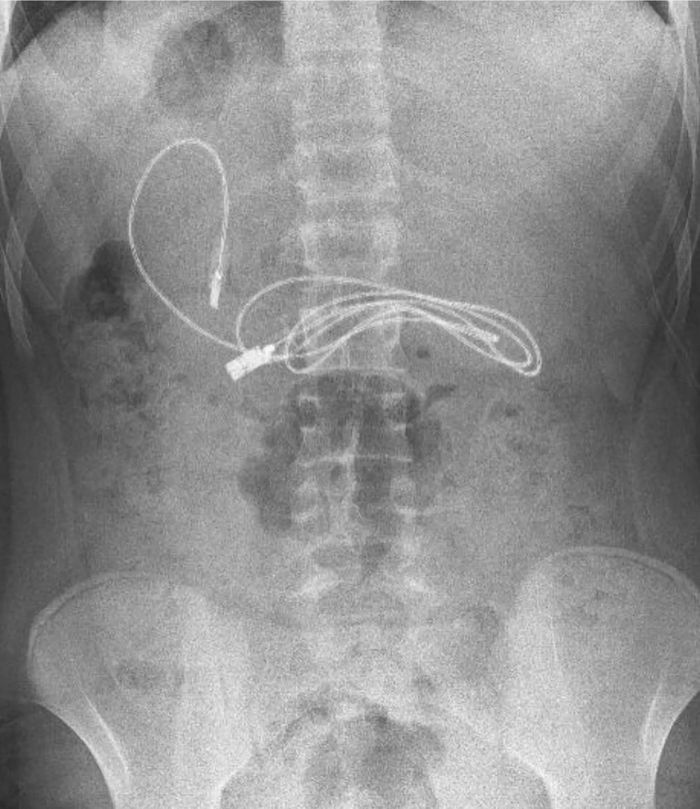

Hình ảnh chụp X-quang thấy rõ dị vật trong người cậu bé 15 tuổi

Cậu bé đến từ Diyarbakir, Thổ Nhĩ Kỳ, được gia đình vội vàng đưa đến bệnh viện sau khi kêu buồn nôn và đau bụng. Chụp X-quang nhanh chóng tiết lộ ra rằng, dây bọc nhựa đang chờ tiêu hóa trong dạ dày cậu bé.

Dây sạc và chun buộc tóc đã được lấy ra khỏi ruột cậu bé bằng phương pháp nội soi.

Bác sĩ chuyên khoa tiêu hóa nhi Yasar Dogan đã yêu cầu thực hiện một thủ thuật nội soi để loại bỏ dây cáp cho cậu bé. Bác sỹ Dogan là trưởng khoa tiêu hóa, gan và dinh dưỡng nhi cùng nhóm của ông đã loại bỏ dị vật sau khi thực hiện thủ thuật nội soi.

Bác sỹ Dogan cho biết: “Rõ ràng là chúng tôi đã gặp khó khăn khi tháo dây cáp ra, vì một đầu của dây cáp đã đi vào ruột non.”

Cuối cùng, sau khi lôi được cuộn dây dài 91 cm ra ngoài, các bác sỹ cũng phát hiện cả một chiếc dây buộc tóc nữa. Vẫn chưa rõ làm thế nào hoặc tại sao cậu bé lại nuốt những dị vật kia vào bụng.

“Sau khi thủ tục kết thúc thành công, bệnh nhân đã được về nhà trong tình trạng sức khỏe tốt ,” bác sỹ Dogan nói thêm.